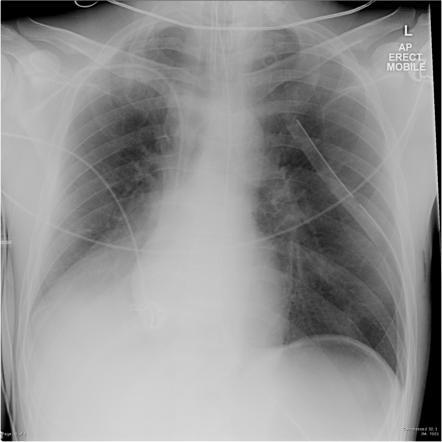

What’s going in in this CXR?

This is a postpneumonectomy patient, with the surgical clips in place.

This was taken POD1 following pneumonectomy. Over the next months, this space will slowly fill with fluid, and then over the following 3 months it will gradually fibrose. The heart and mediastinum will then shift towards this side due to myofibroblast contraction.

The patient will also be missing the 5th or 6th rib, taken as part of the procedure, and surgical clips will be present.